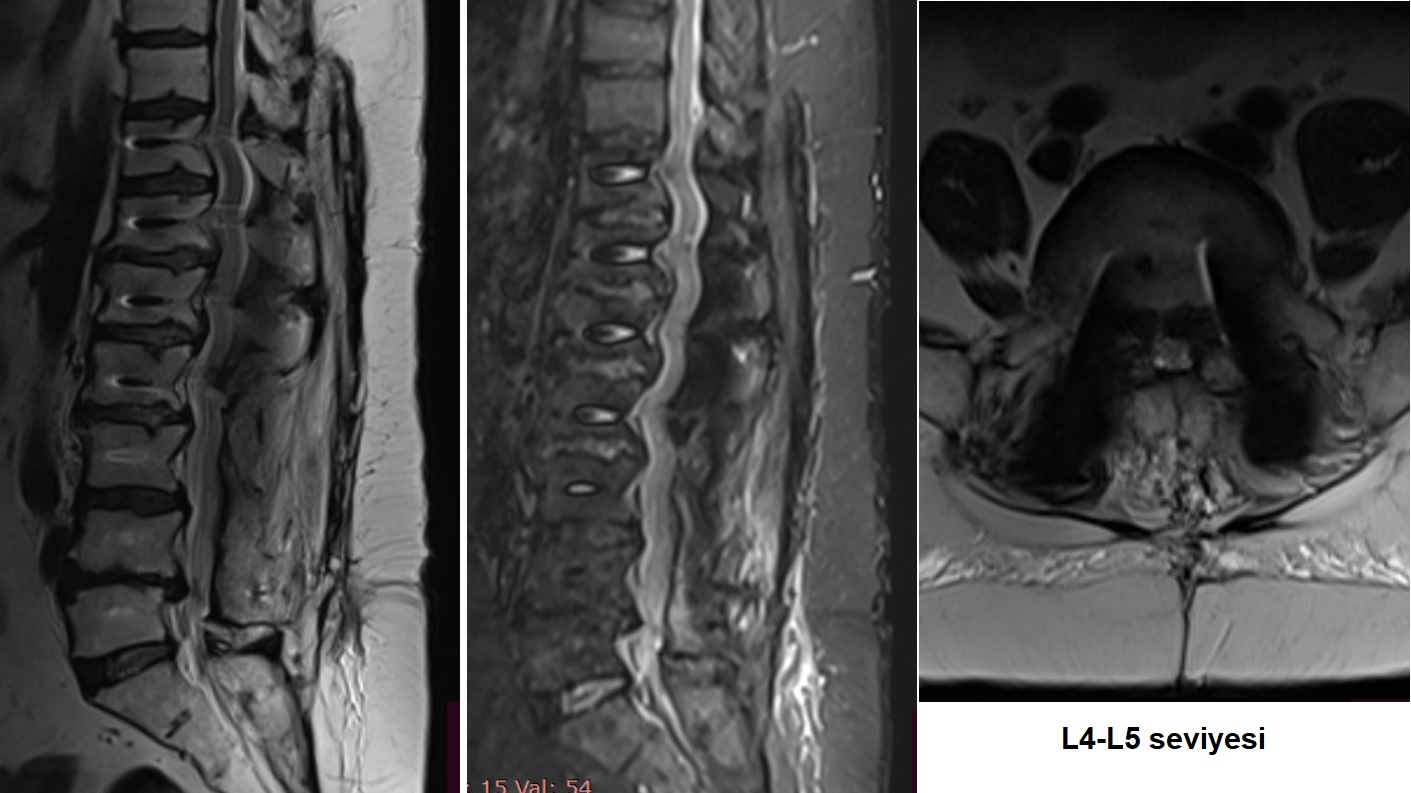

L4-L5 seviyesi

L4-L5 MRG Kesitleri L4-L5 Sağ Taraf L4-L5 Sol Taraf

Resim 5: L4-5 seviyesindeki santral (en üst sıra), sağ foraminal (orta sıra) ve sol foraminal (alt sıra) görüntülerde iki yanlı olarak kanal içinde lateral reseslerin, solda daha belirgin olarak iki yanlı L4-5 foramenlerinin daraldığı görülmekte.

L5-S1 seviyesi

L5-S1 MRG Değerlendirmesi

Resim 6: L5-S1 seviyesi nisbeten daha iyi korunmuştur ve lateral resesler açıktır. Ancak solda gevşeyen L5 vidasının L5 pedikülünün alt duvarını erode ederek forameni daralttığı görülmekte (L4-5 resimleri alt sıra). L5-S1 sağ nöral foramen normaldir (L4-5 resimleri orta sıra).

Sonuç olarak hastada üst uçta (T10-T11) komşu segment dejenerasyonu, alt uçta L4 ve L5 vidalarında gevşeme, L4-5 seviyesinde iki yanlı lateral reses ve foramen stenozu, L5-S1 seviyesinde solda gevşeyen L5 vidasına bağlı olarak foramen stenozu saptandı.